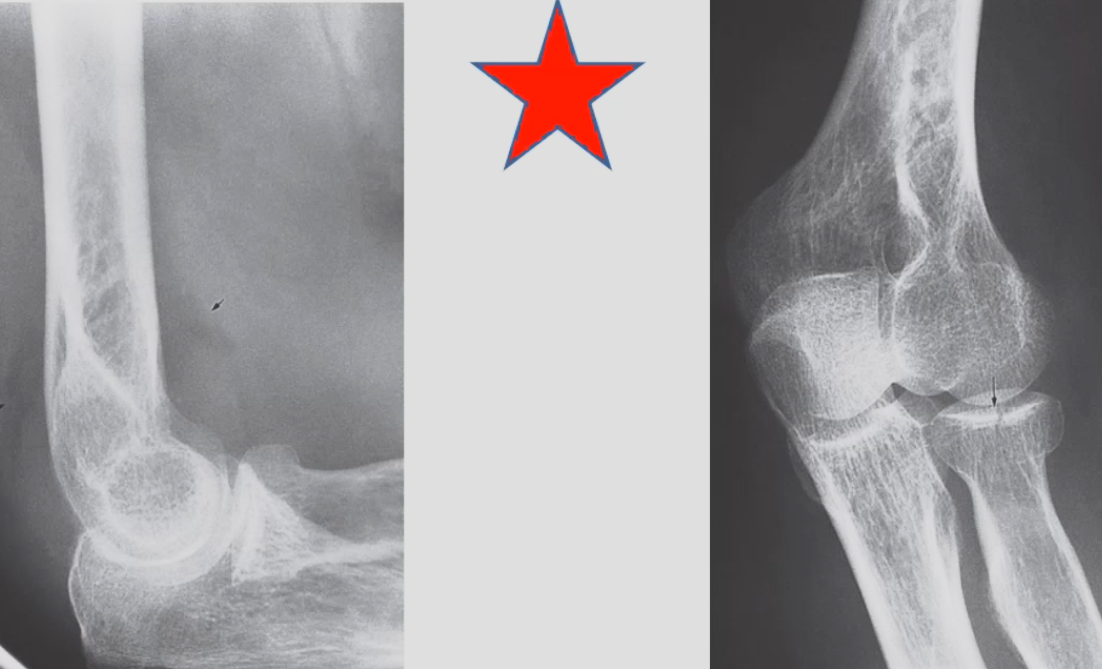

Extension-type supracondylar humeral fracture X-ray elbow (lateral view) of a child with a history of recent trauma